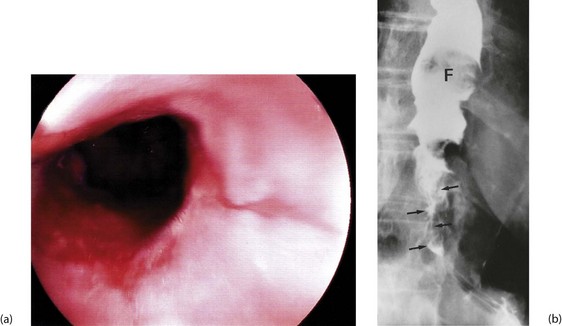

Chest X-ray may show the mediastinal shadow is widened by a dilated oesophagus; sometimes a fluid level in the oesophagus is visible behind the heart Fig. 22.7(b). At endoscopy the typical appearance is of a capacious distal oesophagus, usually with food and fluid residue, and a tight lower oesophageal sphincter that may or may not admit the tip of the gastroscope. It is important to see the oesophago-gastric junction to exclude an occult neoplasm masquerading as achalasia (pseudoachalasia). Barium swallow examination reveals gross dilatation of the oesophagus with a tapering constriction (often described as a ‘bird’s beak’ or ‘rat’s tail’) at the lower end. The constriction barely allows contrast to enter the stomach (see Fig. 22.8). Under fluoroscopic screening, uncoordinated purposeless peristaltic waves can often be seen; these are described as tertiary contractions, distinct from normal coordinated primary and secondary contractions. Oesophageal manometry is the cardinal test for achalasia, demonstrating excessive lower oesophageal sphincter pressure that fails to relax on swallowing, and abnormal peristalsis in patients with a more chronic history.

Pharyngeal pouch is a rare cause of dysphagia. It arises at the junction of pharynx and oesophagus, and probably results from lack of coordination between the inferior constrictor muscle and cricopharyngeus during swallowing. At this point, there is an area of relative weakness known as Killian's dehiscence. The result is a progressive mucosal outpouching between the two muscles. The condition is best diagnosed by barium swallow (see Fig. 22.10). Pharyngeal pouch is easily perforated during endoscopy, and therefore in endoscopy to investigate ‘high’ dysphagia, the procedure should be performed by an experienced endoscopist. Treatment of pharyngeal pouch is by surgical excision from the side of the neck, or via a completely endoluminal approach using a stapler to join the pouch to the oesophagus.